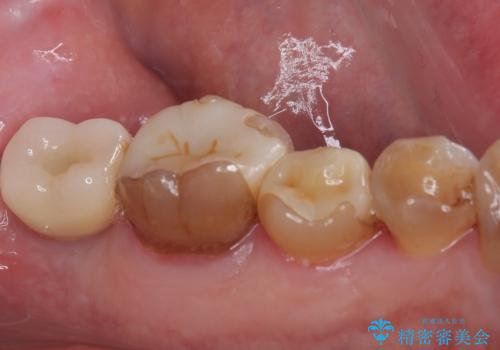

左上の奥2本は他院で根管治療と仮歯まで入れている状態です。根管治療のやり替えは希望されなかったため被せものから治療していくことにしました。

その手前の小臼歯は根尖病変が認められるため根管治療のやり直しからしていくこととしました。